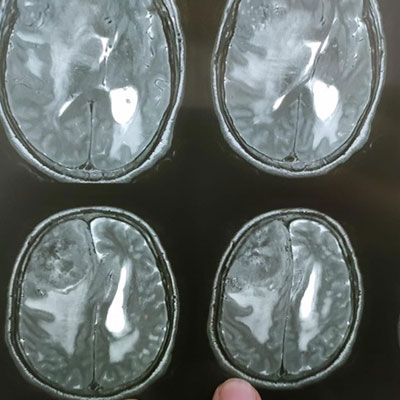

Surgical Highlights